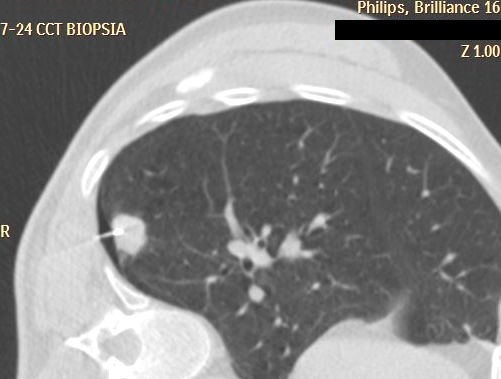

19.2.5. Complications of biopsy and drainage

- Hemorrhage (subcapsular (figure 12.), parenchymal, intraabdominal (figure 13.), intrathoracic, pseudoaneurysm),

- Ptx (thoracic (figure 14.), mediastinal, infraclavicular, in case of subdiaphragmatic intervention),

Image

A

B

Figure 14. – PTX after lung biopsy (A: immediately after biopsy is only a small PTX, B: 5 minutes CT control)